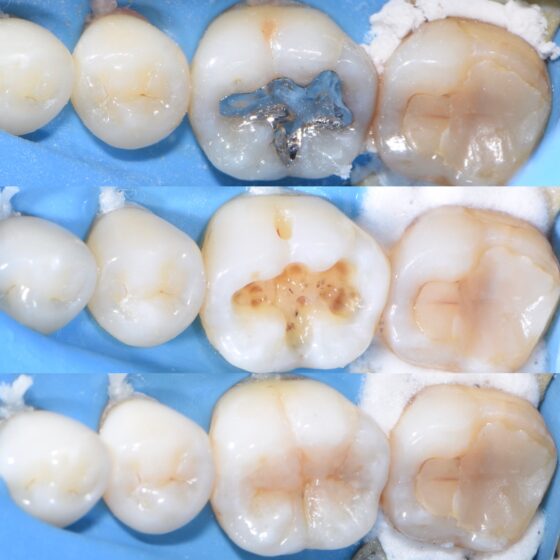

宇部市歯医者 ラバーダム防湿 セラミック治療 歯の神経を守る